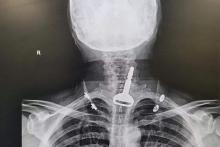

وقتی این مرد پس از حادثه به بخش اورژانس بیمارستان برده شد، پزشکان با انجام تصویربرداری اشعه ایکس توانستند محل قرار گرفتن سوئیچ در مجرای تنفسی این مرد را بیابند. از آنجایی‌که این مرد مشکل قلبی هم داشت، شرایط هم پیچیده‌تر شده بود. اما خوشبختانه عمل لاپاروسکوپی موفقیت‌آمیز بود و این مرد عربستانی از این حادثه جان سالم به‌در برد.